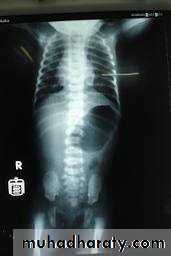

Horse shoe kidney :-*lower poles fused *low positioned kidneys *parallel to spines.*malrotated medially